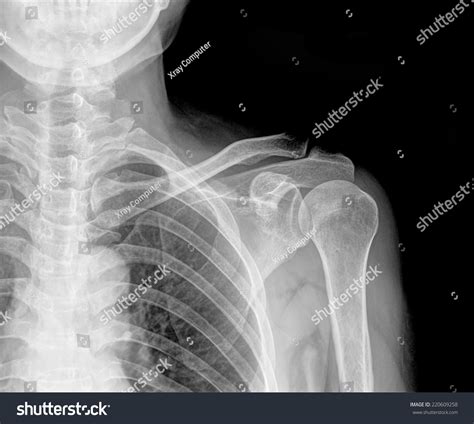

Understanding the significance of a shoulder X-ray normal result is crucial for both medical professionals and patients. A shoulder X-ray is a common diagnostic tool used to evaluate the bones, joints, and surrounding soft tissues of the shoulder. This imaging technique helps identify fractures, dislocations, arthritis, and other abnormalities. However, interpreting a shoulder X-ray normal result requires a thorough understanding of the anatomy and potential pathologies that can affect the shoulder.

The shoulder is a complex joint composed of several bones, muscles, and ligaments. The primary bones involved are the humerus (upper arm bone), scapula (shoulder blade), and clavicle (collarbone). The shoulder joint is a ball-and-socket joint, allowing for a wide range of motion. The rotator cuff, a group of muscles and tendons, plays a crucial role in stabilizing the shoulder and enabling movement.

A shoulder X-ray is a non-invasive imaging test that uses electromagnetic radiation to produce images of the shoulder joint and surrounding structures. This test is often the first step in diagnosing shoulder pain or injury. The X-ray can reveal fractures, dislocations, arthritis, and other bone abnormalities. However, it may not always show soft tissue injuries, such as tears in the rotator cuff or ligaments.